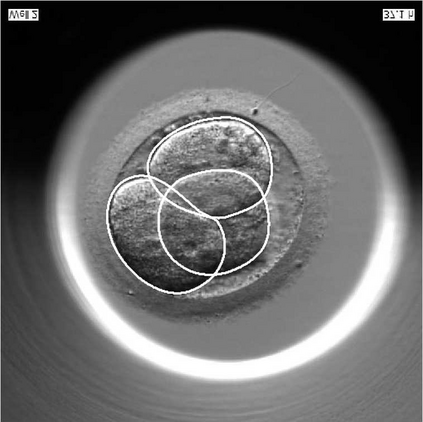

We present a novel method for identification of the boundary of embryonic cells (blastomeres) in Hoffman Modulation Contrast (HMC) microscopic images that are taken between day one to day three. Identification of boundaries of blastomeres is a challenging task, especially in the cases containing four or more cells. This is because these cells are bundled up tightly inside an embryo's membrane and any 2D image projection of such 3D embryo includes cell overlaps, occlusions, and projection ambiguities. Moreover, human embryos include fragmentation, which does not conform to any specific patterns or shape. Here we developed a model-based iterative approach, in which blastomeres are modeled as ellipses that conform to the local image features, such as edges and normals. In an iterative process, each image feature contributes only to one candidate and is removed upon being associated to a model candidate. We have tested the proposed algorithm on an image dataset comprising of 468 human embryos obtained from different sources. An overall Precision, Sensitivity and Overall Quality (OQ) of 92%, 88% and 83% are achieved.